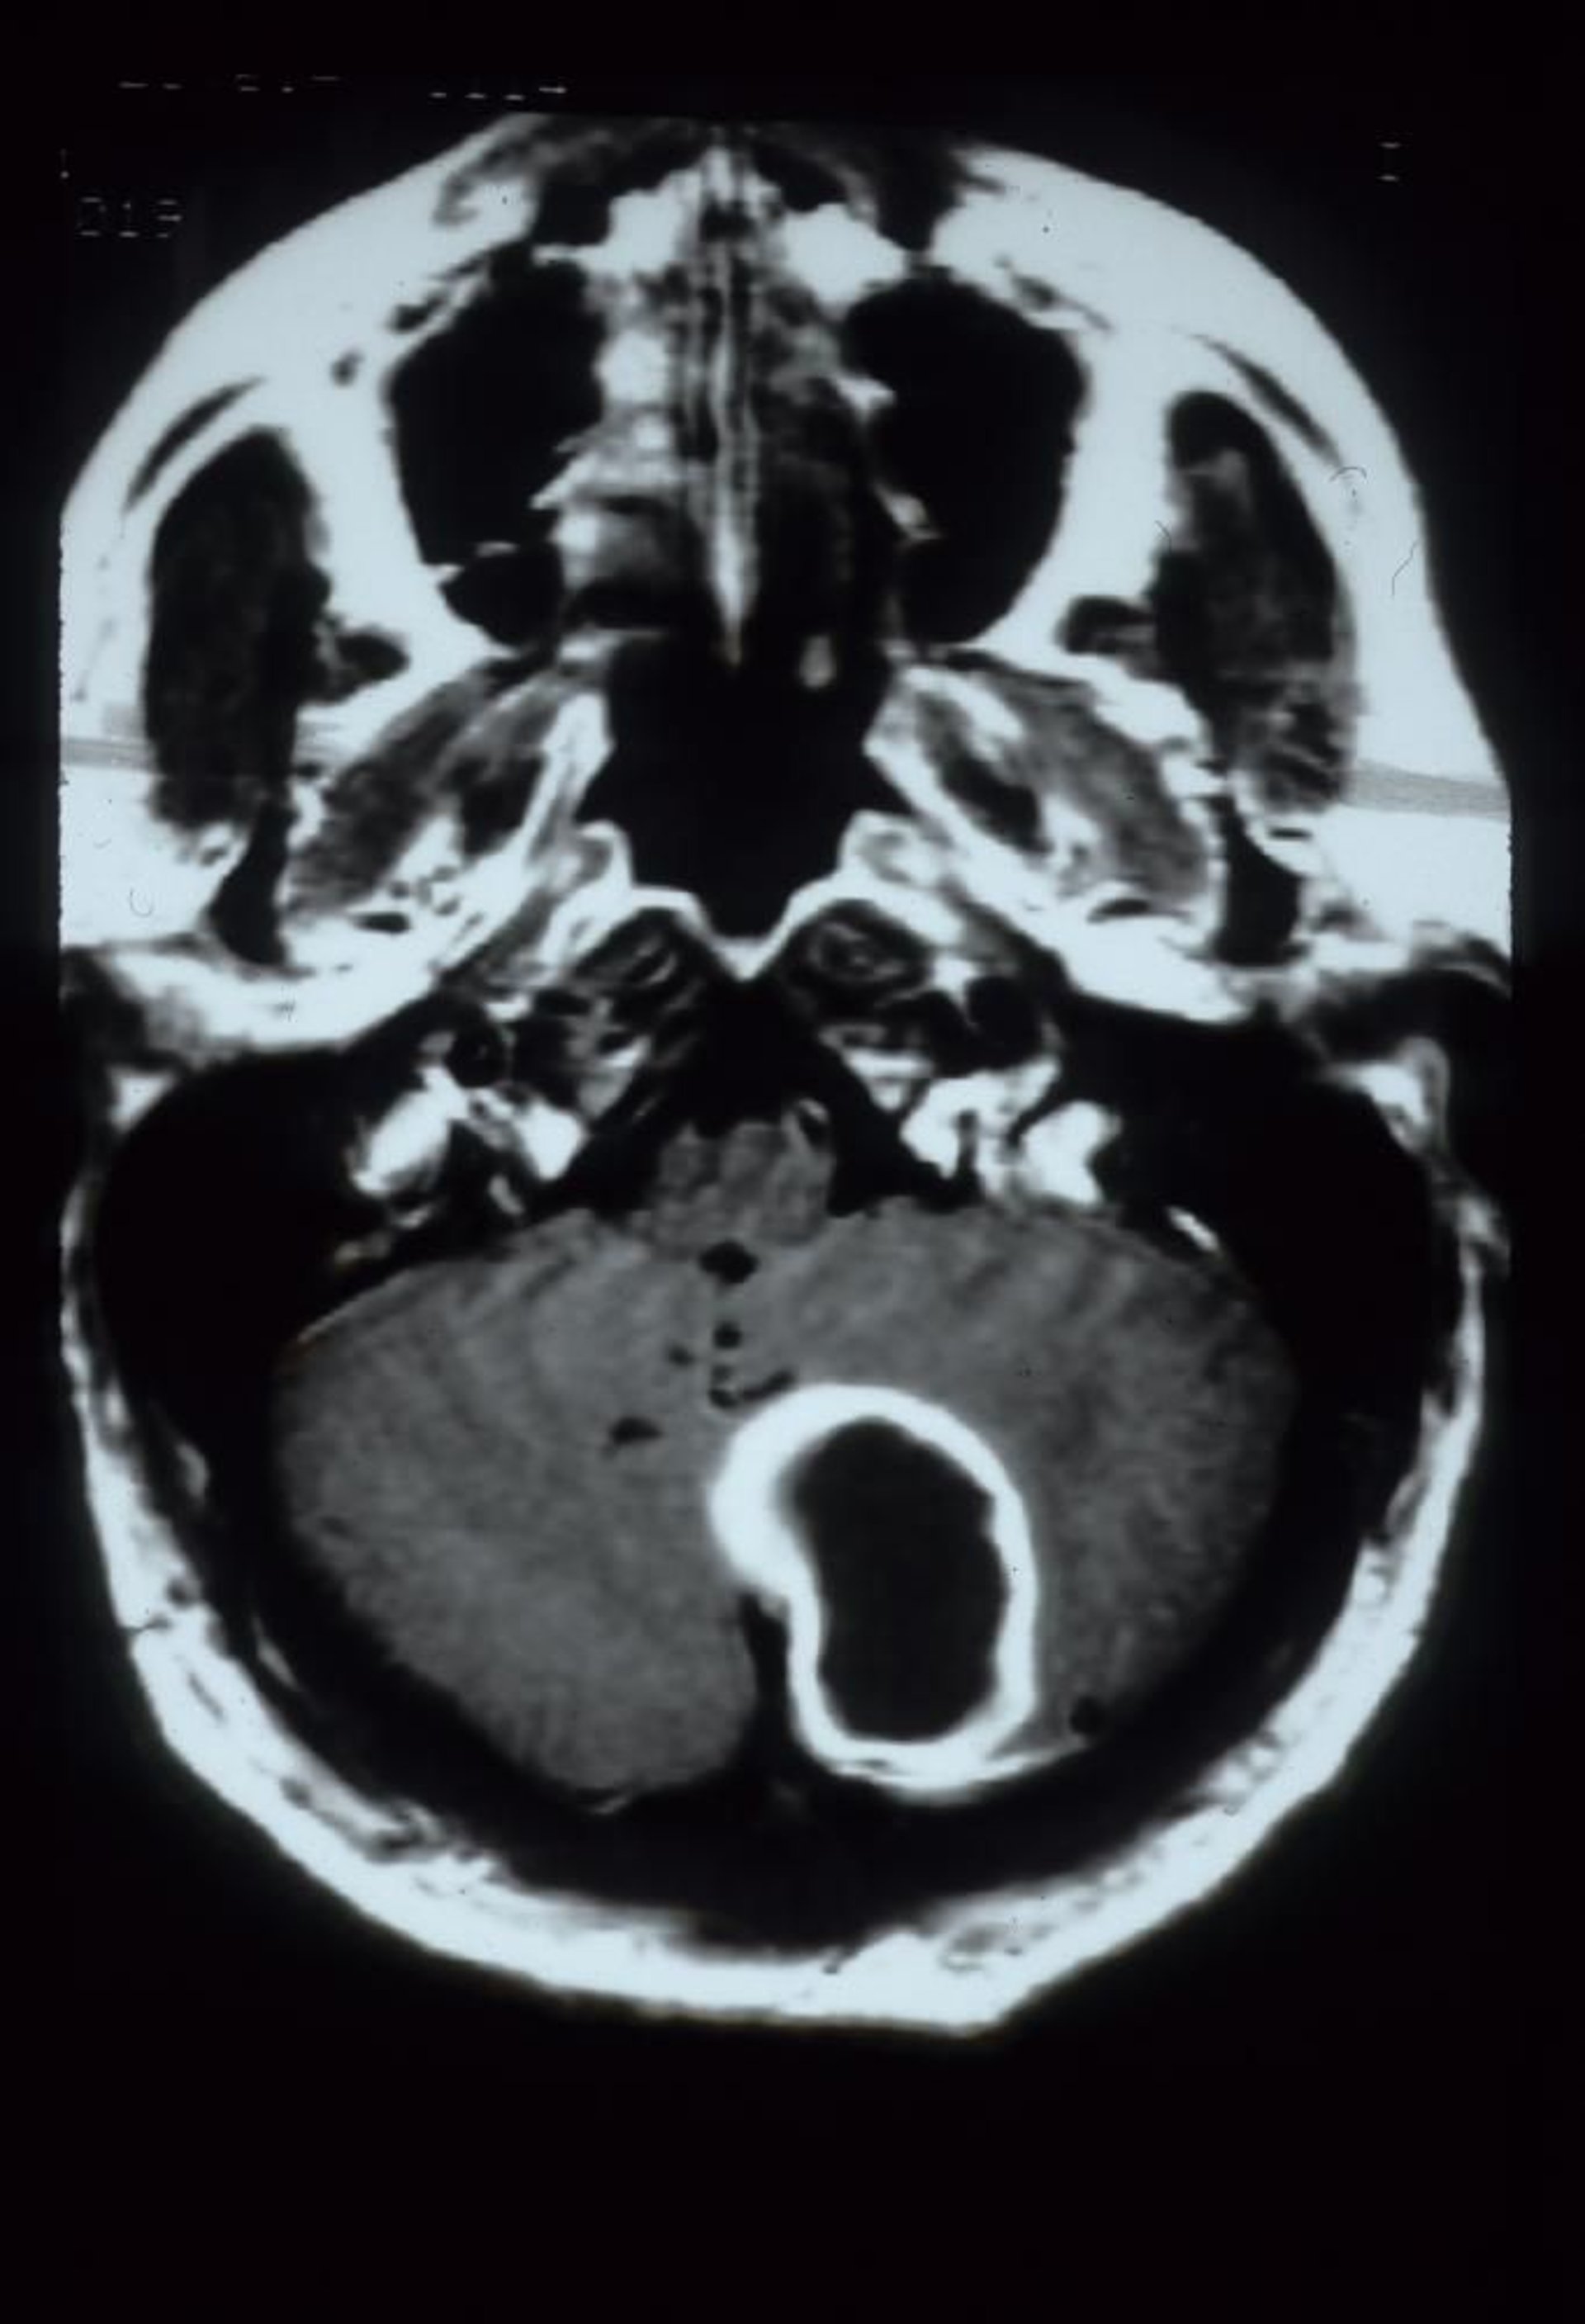

Abscesso cerebelar

Essa RM com contraste de gadolínio mostra abscesso cerebelar, que aparece como um halo de contraste em uma grande lesão cavitária no hemisfério cerebelar esquerdo.

Courtesy of John E. Greenlee, MD.